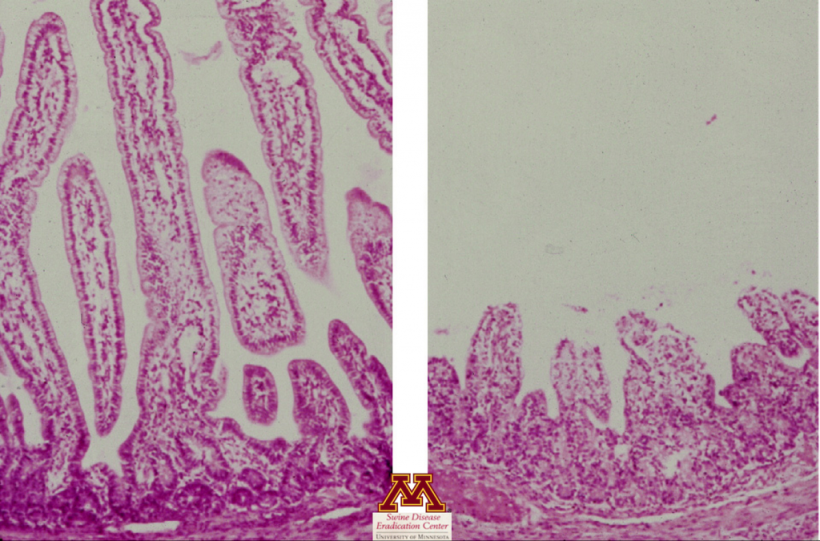

- Valuta la presenza di lesioni tissutali (atrofia dei villi dell'intestino tenue) che possono fortemente suggerire la presenza di malattia.

- Conferma l'atrofia dei villi che suggerisce un'enterite virale

- Positivo: conferma della malattia, ma non della causa della malattia.